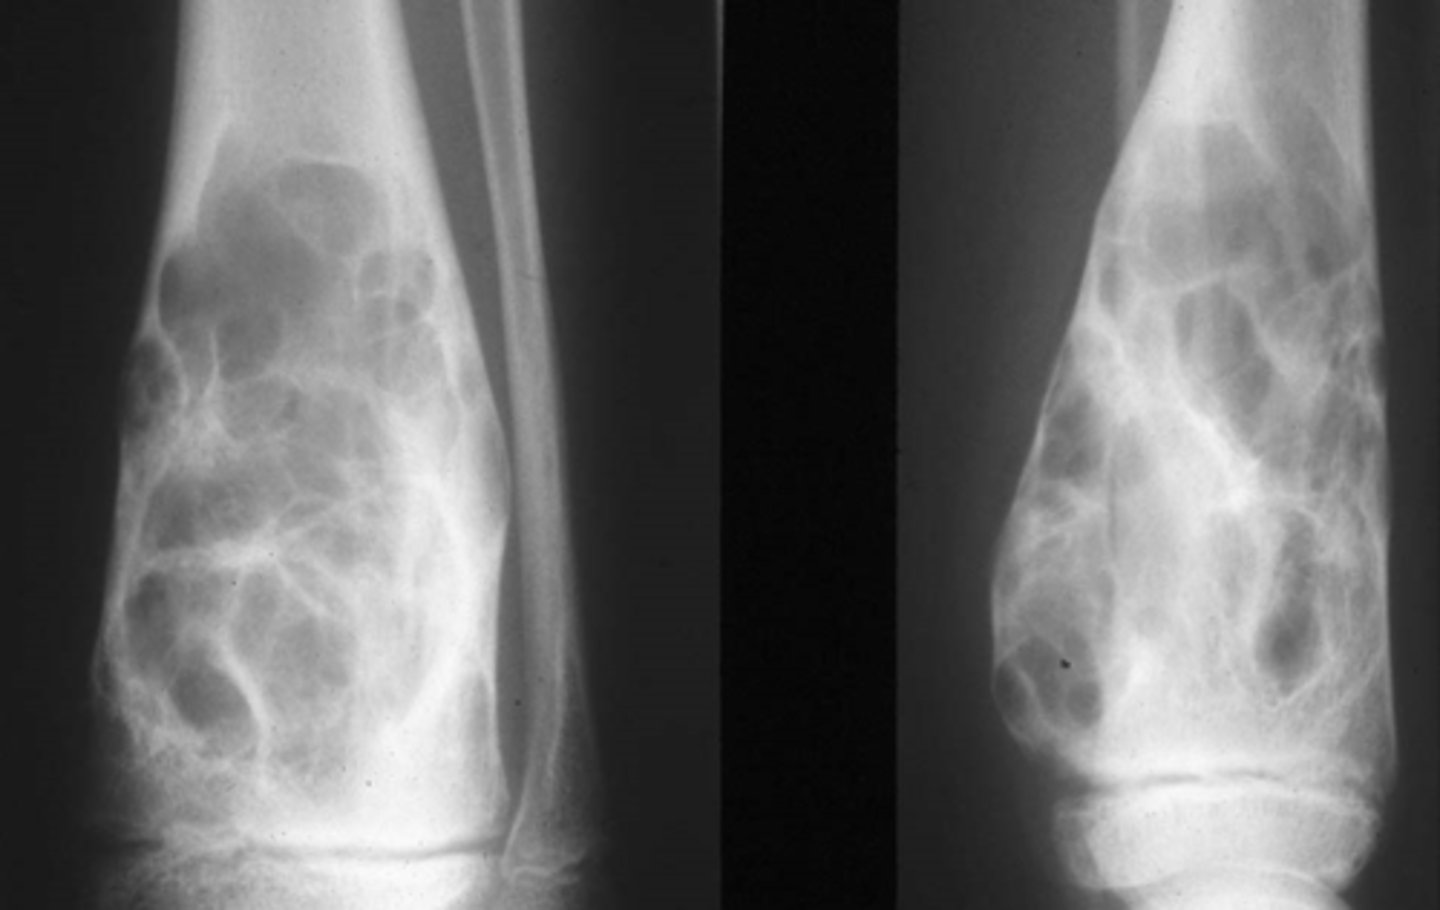

Vignette # 19

Sex: Male

Age: 22

Chief Complaint: Patient presents with insidious onset of wrist pain that started one week ago. Father has a history of Hodgkin's.

Objective Findings: Distal radius is warm, swollen, and tender, Decrease ROM is all planes with pain, x-ray shows a soap bubbly lesion that is eccentrically located Diagnostic imaging: X-ray

1. What are the differential diagnoses? (Choose 3)

a. Osteomyelitis

b. GCT(20-40, soap bubble, epi/meta)

c. ABC(<20, eccentrically, blood filled, dia/meta)

d. Enchondroma (most common bbt of the hand)

e. Osteochondroma(most common bbt of the appendicular skeleton-

pedunculated or sessile)

f. Chondroblastoma(<20, epi/meta)

g. Osteosarcoma

Surgical consult

Curettage

Brace/Stabilize joint

Chief Complaint: Patient presents with insidious onset of wrist pain that started one week ago. Father has a history of Hodgkin’s.

2. What are the possible treatment options or next step for this condition? (Choose3)

a. Oncologist

b. Surgical consult

c. MRI

d. Antibiotics

e. Curettage

f. ER

g. Brace/Stabilize joint

h. Refer for biopsy

Pathological fracture

Complete resolution

Malignant degeneration

3. What are the possible future consequences of this condition? (Choose 3)

a. Complete resolution

b. Septicemia

c. Vascular compromise

d. Neurological deficit

e. Malignant degeneration

f. Pathological fracture (all bbt can cause pathological fx)

g. Lymphedema (usually cause by damage to or removal of lymph nodes

during cancer treatment)

h. Bony fusion (bone graft?)